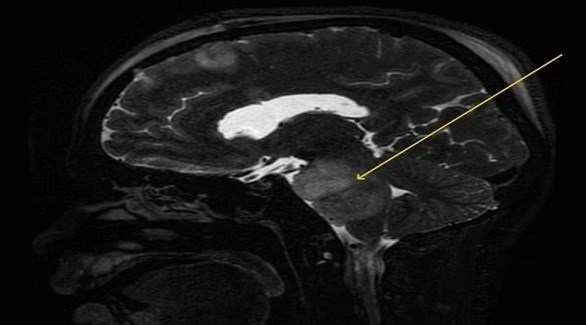

وكشف تصوير بالرنين المغناطيسي عن كتلة من الأنسجة تدل على وجود ورم دبقي جسري، وهو نوع من ورم الدماغ ينمو على جذع الدماغ، وهو الجزء الذي يربط العضو بالعمود الفقري، بالإضافة إلى نزيف داخلي داخل الدماغ نفسه.

ومن المستحيل إزالة الأورام الدبقية الجسرية جراحياً بسبب مدى ترابطها مع جذع الدماغ الفعلي، وتم إرسال الرجل لإجراء عملية جراحية، حيث قطع الجراحون دماغه لتخفيف الضغط داخل جمجمته، والذي نتج عن تراكم السوائل في الدماغ. وبعد ثمانية أيام من الشفاء، خضع الرجل لدورة علاج إشعاعي لمدة ستة أسابيع في محاولة لقتل الورم.